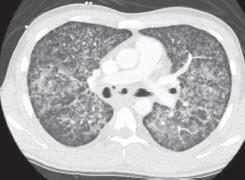

About 3.4% of the hospitalized tubercular patients need admission to the intensive care unit (ICU). Patients requiring ICU admission had a poor prognosis and high mortality rate (60 vs 25%) as compared to other causes of severe pneumonia. The most common indication for tuberculosis-related ICU admission is acute respiratory failure due to pneumonia or acute respiratory distress syndrome (ARDS) (with or without miliary tuberculosis) followed by septic shock with multiple organ dysfunction, adrenal insufficiency, and neurological involvement, especially tubercular meningitis. Tuberculosis patients who require admission to ICU are mostly immunocompromised [human immunodeficiency virus (HIV) coinfection] and have underlying miliary tuberculosis or disseminated tuberculosis. Pulmonary tuberculosis presenting as ARDS is a rare phenomenon, but a most common cause of admission of tuberculosis patients to ICU. Tuberculous meningitis is the most severe form of tuberculosis with mortality more than 60% and residual neurological disability in 25% cases. Tuberculosis-related septic shock has been found in only 1% of all septic shock patients admitted to ICU. Patients with tuberculosis with refractory shock should be suspected for adrenal insufficiency. A trial of physiologic stress replacement dose of hydrocortisone (200-300 mg) should be given to all critically ill patients with vasopressor-dependent shock after correcting other causes. Diagnosis and treatment of tuberculosis in critically ill patients has various challenges, namely appropriate sample collection, issues with the route of administration, drug absorption, bioavailability, dose modification in hepatic and renal dysfunction, and interaction with other drugs. Chaudhry D, Tyagi D. Tuberculosis in Intensive Care Unit. Indian J Crit Care Med 2021;25(Suppl 2):S150-S154.

约3.4%的住院结核病患者需要入住重症监护病房(ICU)。与其他严重肺炎病因相比,需要入住ICU的患者预后较差,死亡率较高(60%对25%)。与结核病相关的ICU入院最常见的指征是肺炎或急性呼吸窘迫综合征(ARDS)(伴或不伴粟粒性结核病)导致的急性呼吸衰竭,其次是伴有多器官功能障碍、肾上腺功能不全和神经受累(尤其是结核性脑膜炎)的感染性休克。需要入住ICU的结核病患者大多免疫功能低下(合并人类免疫缺陷病毒(HIV)感染),并患有潜在的粟粒性结核病或播散性结核病。表现为ARDS的肺结核是一种罕见现象,但却是结核病患者入住ICU最常见的原因。结核性脑膜炎是结核病最严重的形式,死亡率超过60%,25%的病例有残留神经功能障碍。在所有入住ICU的感染性休克患者中,仅1%发现与结核病相关的感染性休克。患有结核病且休克难治的患者应怀疑有肾上腺功能不全。在纠正其他病因后,应给予所有依赖血管活性药物的重症患者生理应激替代剂量的氢化可的松(200 - 300毫克)进行试验。重症患者结核病的诊断和治疗面临各种挑战,即合适的样本采集、给药途径问题、药物吸收、生物利用度、肝肾功能不全时的剂量调整以及与其他药物的相互作用。乔杜里D,蒂亚吉D。重症监护病房中的结核病。《印度重症监护医学杂志》2021;25(增刊2):S150 - S154。